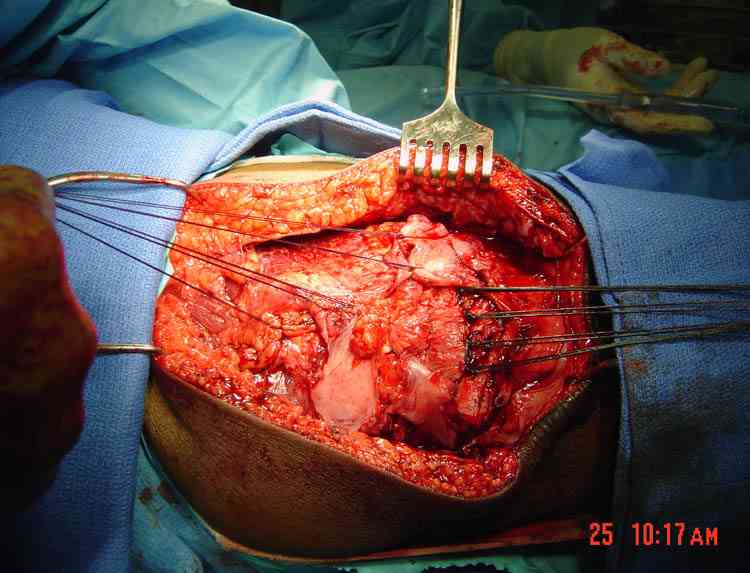

На снимке восстановление разрыва quad связки, только швы завязывается внизу надколенника, и примерный рисунок техники.

В приложении фото пациента с переломом надколенника 3 месячной давности. После мобилизации отломков, 4 главой мышцы бедра и полного разгибания голени оставался диастаз между костными фрагментами в 2 см. В связи с этим наложили модуль из аппарата Илизарова - 2 опоры и 2 спицы (в верхнем полюсе надколенника и верхней трети большеберцовой кости). Очень медленно (в течение 15 минут) путем накручивания гаек на стержнях растянули 4 главую мышцу бедра и устранили диастаз. Аппарат демонтировали и выполнили остеосинтез <стягивающей петлей>. Через 6 месяцев фиксаторы удалены. Автор данного <хирургического трюка> профессор из Австрии Vilmos Vecsei (<Гений ортопедии>, 2004, № 4, С. 94-95). Ваш случай не совсем идентичный по давности травмы и малой величине дистального отломка, но описанный <трюк> может оказаться полезным и при выполнении операции, которую рекомендует Джолдас.